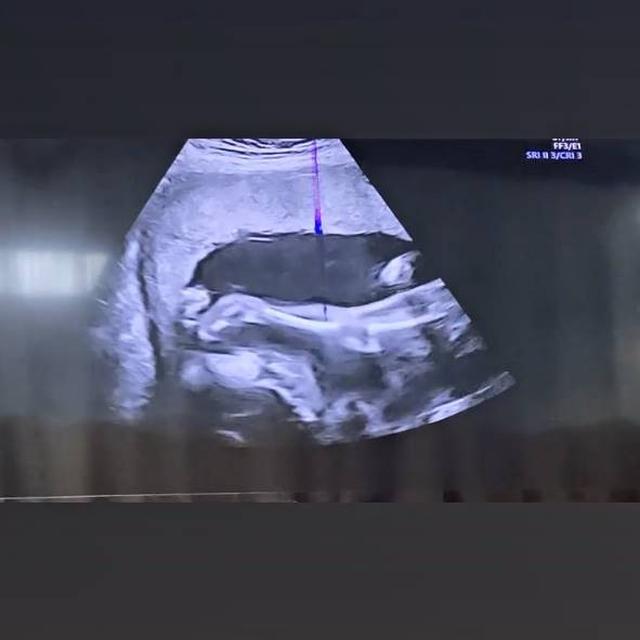

Paling baru ia mengunggah video hasil USG buah hatinya yang tengah aktif bergerak di dalam kandungan.

"Masyaallah,Tabarakallah…Aduhhh duuduuu…dedek lagi mau salto yaa,masyaallah kakinya panjang sekali anakku.sehat-sehat yaa sayang di dalam peyutt mamake.❤️" tulis Uut dalam keterangan Instagramnya.

2. Dalam unggahan terbarunya ia memperlihatkan hasil USG janinnya yang terlihat lincah